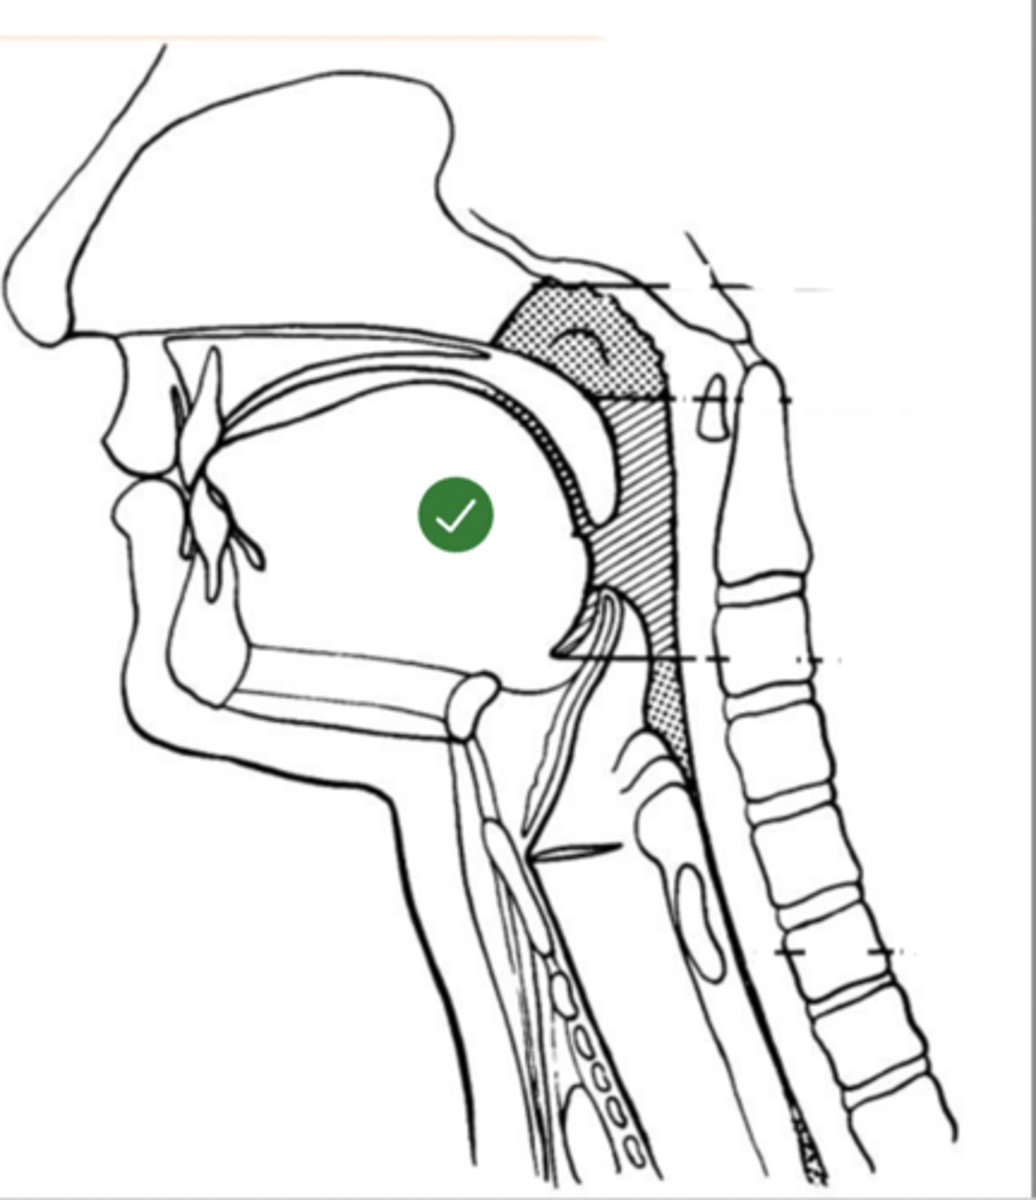

Label Nasopharynx (lateral view)

Label Nasal cavity (lateral view)

Label oropharynx (lateral view)

Label hypopharynx/ hylolarynx

Label tongue (lateral view)

Label soft velum/ palate (lateral view)

Label hard palate (lateral view)

Label mandible (lateral view)

Label base of tongue (lateral view)

label hyoid bone (lateral view)

Label epiglottis (lateral view)

label Line of true vocal folds (lateral view)

label Thyroid cartilage (anteriorly) (lateral view)

Label posterior cricoid (lateral view)

Label esophagus (lateral view)

label anterior tongue (lateral view)

Label posterior/ back of tongue (lateral view)

Label velum/ soft palate (lateral view)

Label thyroid cartilage (lateral view)

Label trachea (lateral view)

Label upper esophageal sphincter (lateral view)

Label posterior pharyngeal wall (lateral view)